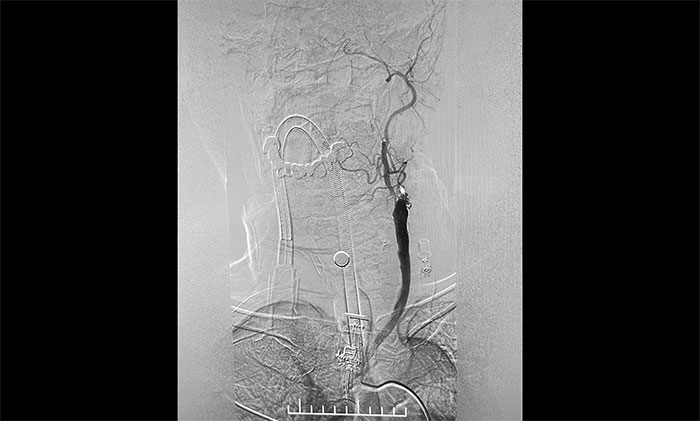

▲ DSA确诊左侧颈内动脉闭塞

脑血管造影显示,左颈总动脉起始段、下段中度狭窄,左颈外动脉起始段重度狭窄,左颈内动脉起始段闭塞,远端颈内动脉缓慢显影至眼动脉;左椎动脉、左大脑后动脉、基底动脉显影,左椎V4段经侧枝向左侧枕动脉代偿供血至左颈外动脉;右颈内动脉起始段轻度狭窄。

术中,超滑导丝、多功能导管经过反复尝试顺利通过左颈内动脉起始段,到达左颈内动脉远端显影段,路图见远端血管通畅,左大脑中动脉显影;随后,微导丝经多功能导管置于左颈内动脉海绵窦段,经微导丝送入保护伞至左颈内动脉岩骨垂直段并释放,再沿保护伞微导丝送入4x30mm球囊于左颈内动脉起始段,给予球囊扩张,撤除球囊后造影见左颈内动脉起始段再通,左颈内动脉、左大脑中动脉显影;最后,送入9x50mm支架,释放于左颈内动脉颈段至左颈总动脉末段,造影见左颈内动脉起始段显影明显改善,左颈内动脉、左大脑中动脉、左大脑前动脉显影可,行3D造影见左颈内动脉颈段显影改善。行支架CT见支架成形可,行XperCT未见颅内出血。